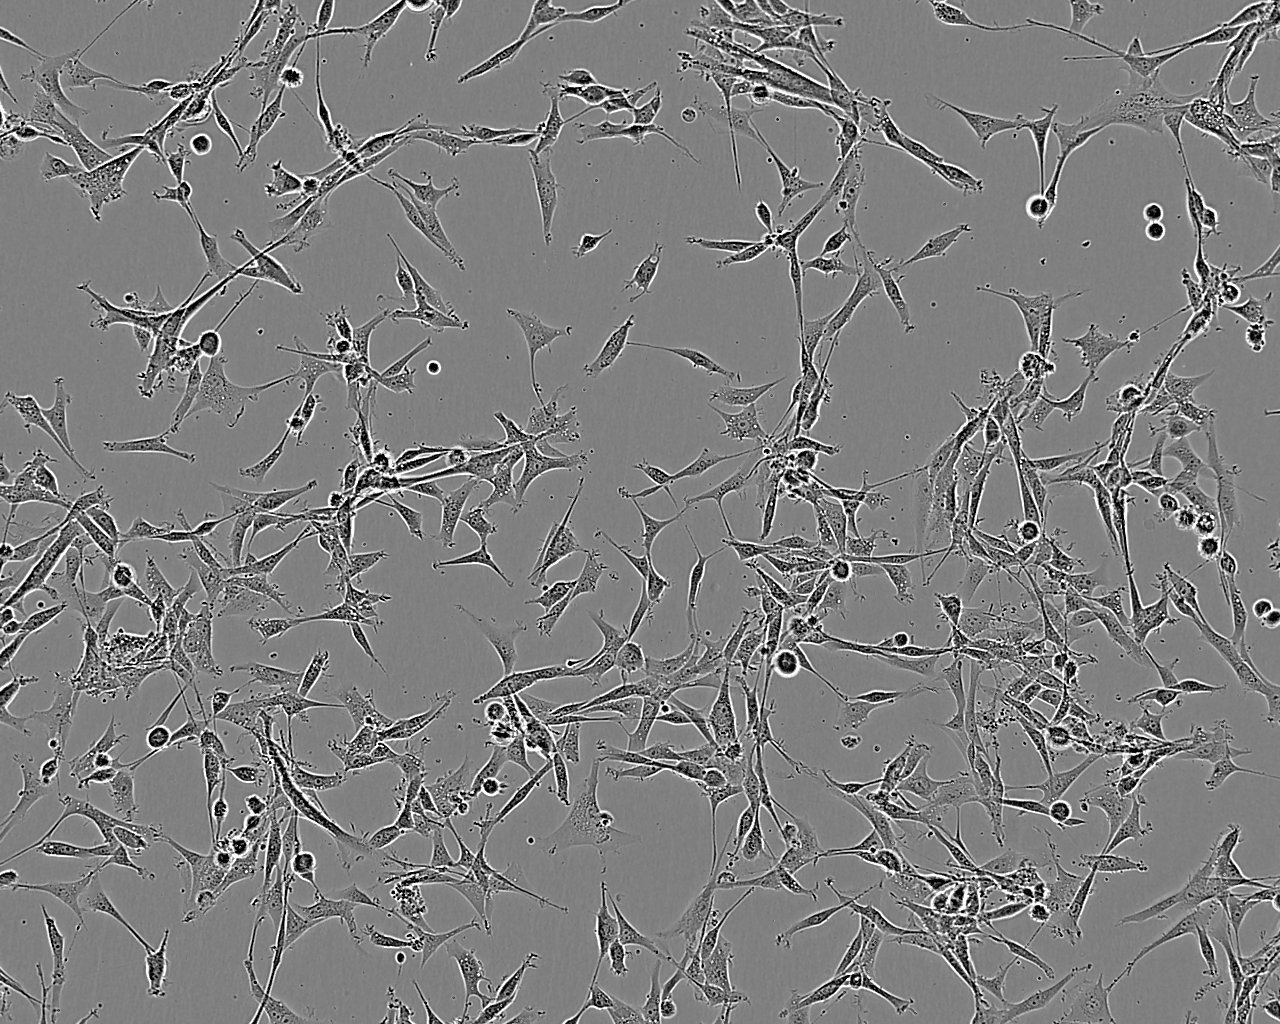

细胞形态:上皮细胞样

细胞生长:贴壁

细胞生长特性:悬浮生长

细胞形态特性:淋巴母细胞样